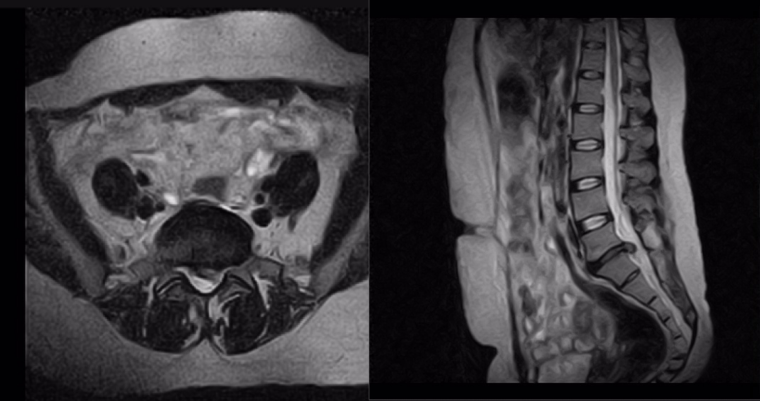

Рис. – МРТ пояснчиного отдела позвоночника. Грыжа м/п диска L5-S1 c каудальной миграцией слева.